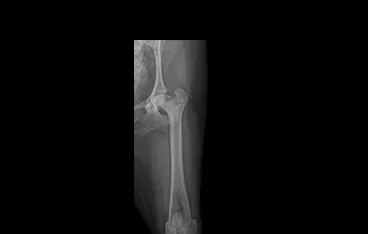

• TPLO 수술 전

TPLO 수술 후